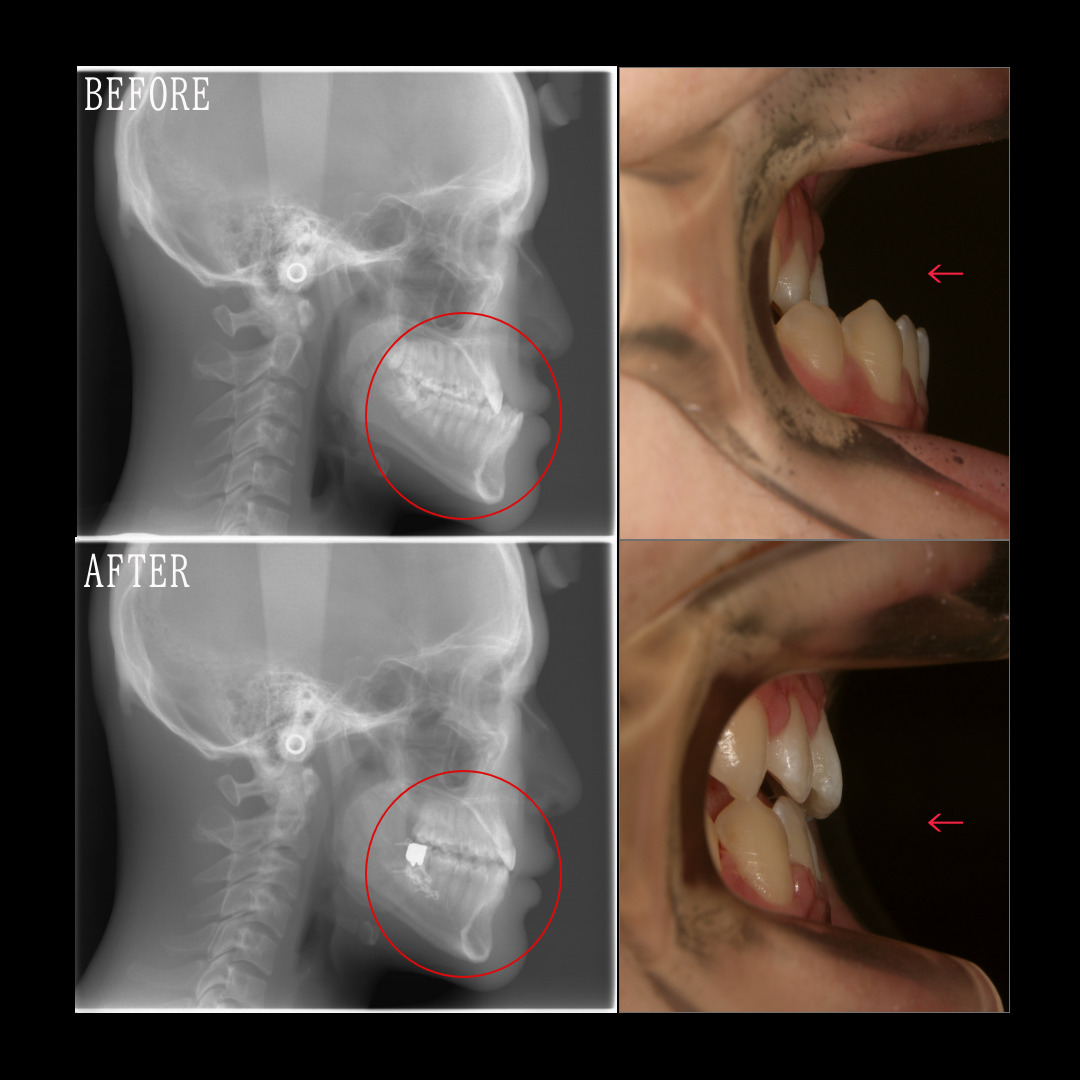

症例紹介

矯正治療の症例・治療内容・費用などを以下の記事で掲載しています。

Check!口ゴボ特集

ただ歯を並べるだけではない口ゴボの矯正治療。

アンカースクリューや抜歯についても詳しくお伝えします。

口ゴボの状態とは

一般的な矯正治療との大きな違い

- ①口ゴボの方へ抜歯をご提案する理由

- ②アンカーロス(固定源喪失)とアンカースクリューの関係

- ③実際に歯が動く様子を動画で見てみよう

- ④口ゴボに関する症例を見る